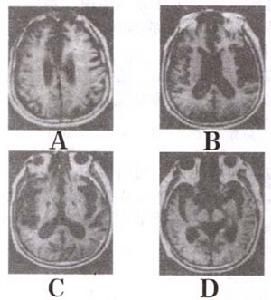

小腦萎縮症確診方法之一,是利用核磁共振成像(MRI)掃瞄腦部,可以見到病變進行中的小腦萎縮。最精確的診斷法,就是DNA分析,可以分辨本症的不同類型。不是所有類型的脊髓小腦萎縮症都會遺傳,所以患者的子女可以接受DNA檢查,以便得悉他們會否有發病的危險。